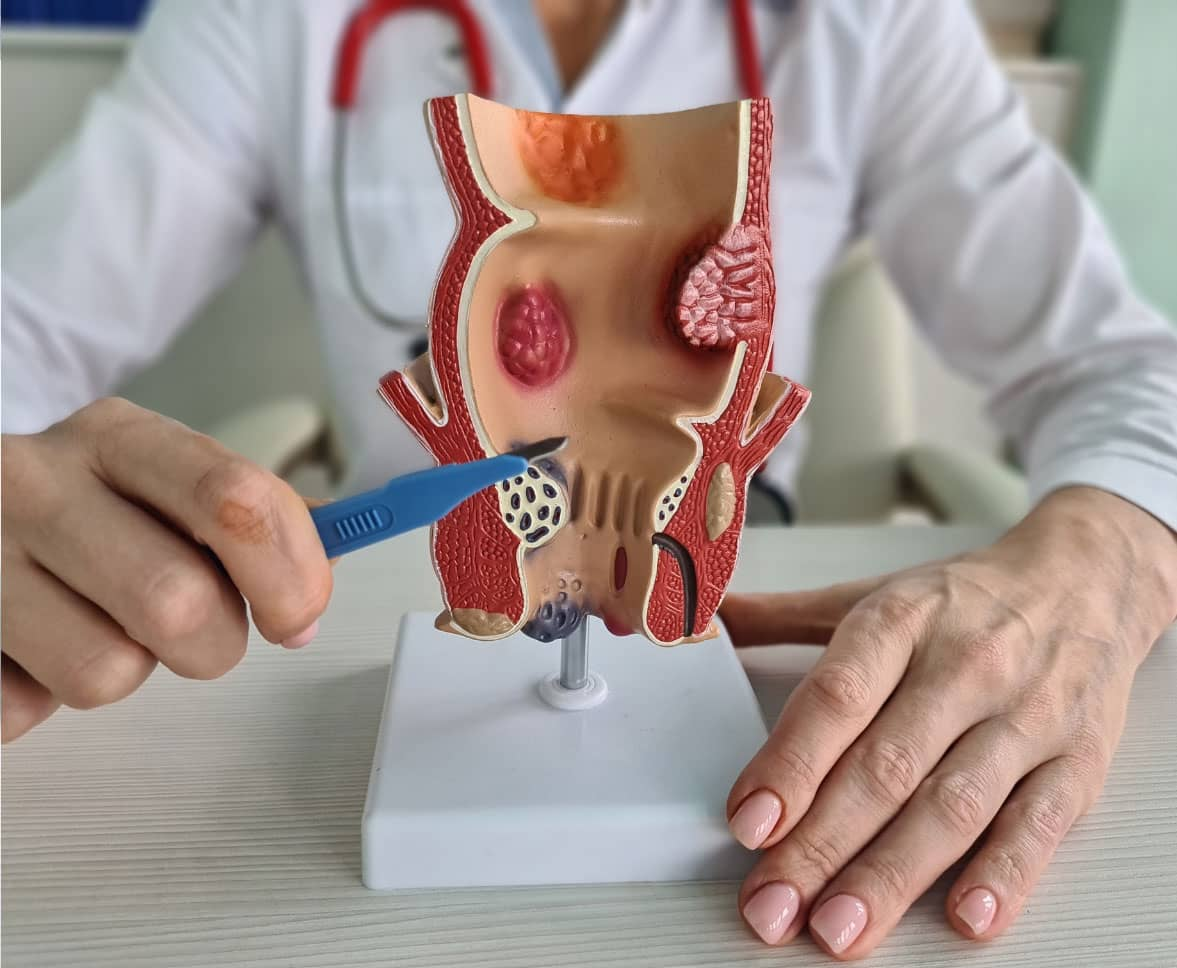

An anorectal abscess is a painful collection of pus near ...

If you experience recurring pus discharge or pain around the anal ...

If you have been dealing with pain, swelling, or pus near the anus that keeps coming back ...

At Karan Hospital, understanding your condition is the first step to better ...